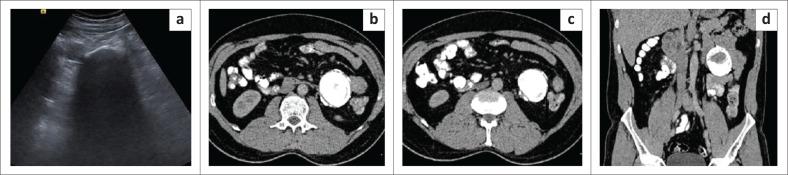

The mesentery is a broad fan-shaped fold of peritoneum that suspends the loops of small intestine from the posterior abdominal wall. Although primary neoplasms arising in the mesentery are rare, the mesentery is a major avenue for the dissemination of tumours, which can spread through hematogenous, lymphatic, direct or peritoneal seeding. Imaging helps in the diagnosis of these tumours and aids in directing appropriate treatment by assessing their size, extent and relationship with adjacent structures. The aim of this article is to describe the spectrum of imaging findings of the various mesenteric lesions using ultrasound and CT.

Evaluation of the mesentery is often neglected during routine ultrasound (US) because of inadequate training and unfamiliarity with the common US features encountered with mesenteric disease. CT plays an essential role in the diagnosis of mesenteric disease. Knowledge of imaging characteristics of various mesenteric lesions helps in timely diagnosis and management.

肠系膜是腹膜的一个宽阔扇形褶皱,将小肠袢从腹后壁悬吊起来。虽然起源于肠系膜的原发性肿瘤很少见,但肠系膜是肿瘤播散的主要途径,肿瘤可通过血行、淋巴、直接蔓延或腹膜种植扩散。影像学有助于这些肿瘤的诊断,并通过评估其大小、范围以及与相邻结构的关系来指导适当的治疗。本文旨在描述使用超声和CT对各种肠系膜病变的影像学表现范围。

由于培训不足以及对肠系膜疾病常见超声特征不熟悉,在常规超声(US)检查中对肠系膜的评估常常被忽视。CT在肠系膜疾病的诊断中起着至关重要的作用。了解各种肠系膜病变的影像学特征有助于及时诊断和处理。